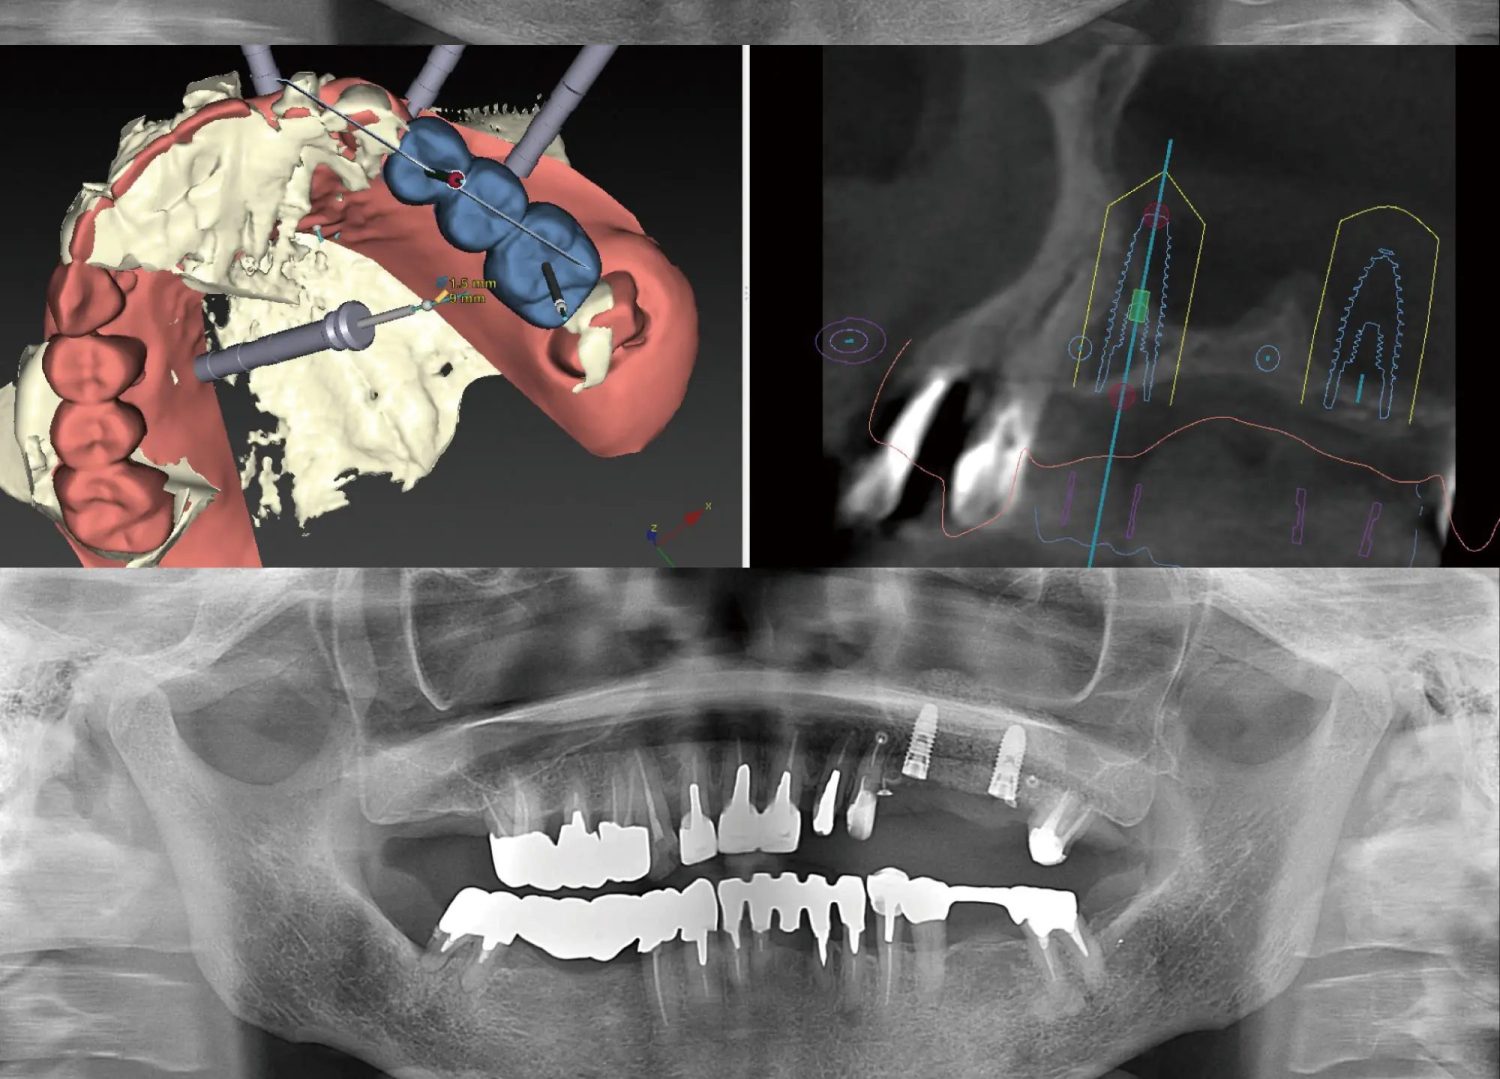

【術前】 【インプラントの光機能化】 【術後】

インプラント治療の症例を紹介します。

下顎の小臼歯が欠損した50歳女性の方は、「自分の歯を極力削らない」「おいしく食事をしたい」「入れ歯の煩わしさから解放されたい」というご希望からインプラントを選択されました。見た目や機能の回復だけでなく、今後の健康維持のために原因への対処や定期的なメンテナンスに取り組まれています。

【治療部位】下顎

【治療期間】4ヶ月間

【治療回数】約10回

【リスク】インプラントが感染することがある

【治療費用】精密検査:16,000円(税込)

一次手術:227,000円(税込)

※手術管理費、仮歯代含む

上部構造:195,000円(税込)

※アバットメント代含む

合計:438,000円(税込)